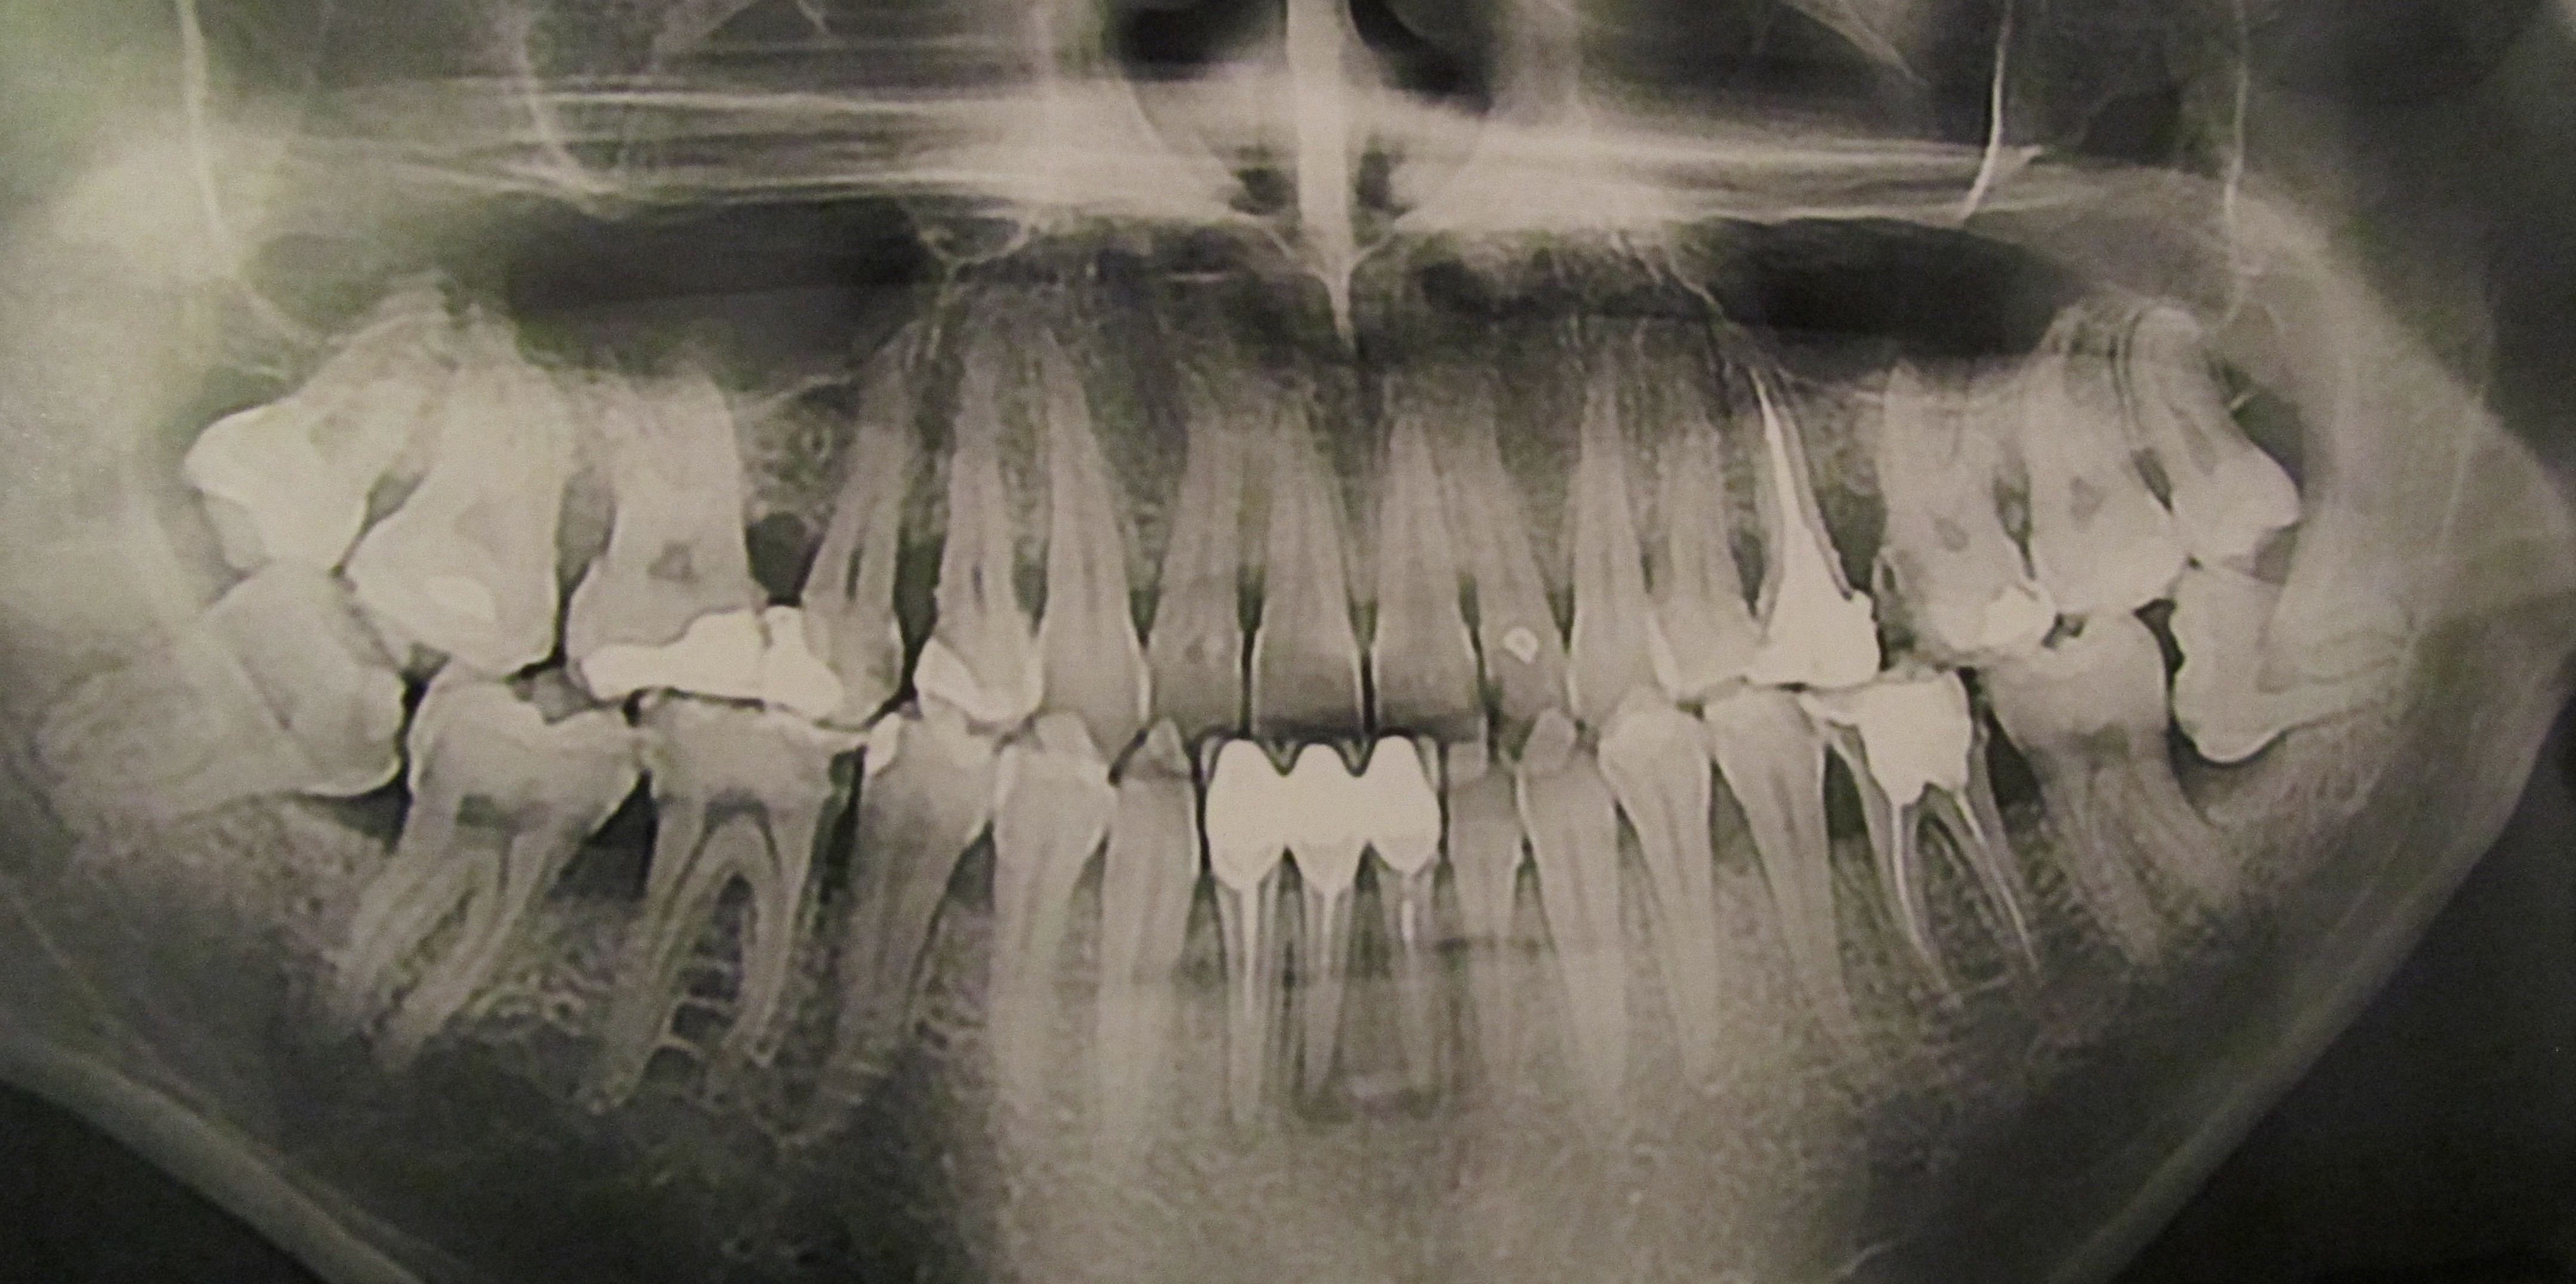

paradontit Опубликовано 12 ноября, 2016 Поделиться Опубликовано 12 ноября, 2016 Снимок в 2013 годуСнимок в этом году, лечения не было никакогоДорогие парадонтологи, посоветуйте метод лечегия в данной ситуации. Очень интересуют независимые мнения. Ссылка на комментарий

red_butler Опубликовано 15 ноября, 2016 Поделиться Опубликовано 15 ноября, 2016 Какая стадия парадонтита? Для определения степени, нужен очный осмотр и зондирование, только по ОПГ тянет на среднюю степень. Возможно ли его вылечить? можно стабилизировать Какой метод и для каких зубов подходит? Открытый/закрытый кюретаж, Вектор, фотодинамические процедуры? нужен очный осмотр Не представляю, что с воспалением на корнях можно делать? Коронки ношу чуть больше пяти лет. снять коронки и перелечивать. Ссылка на комментарий